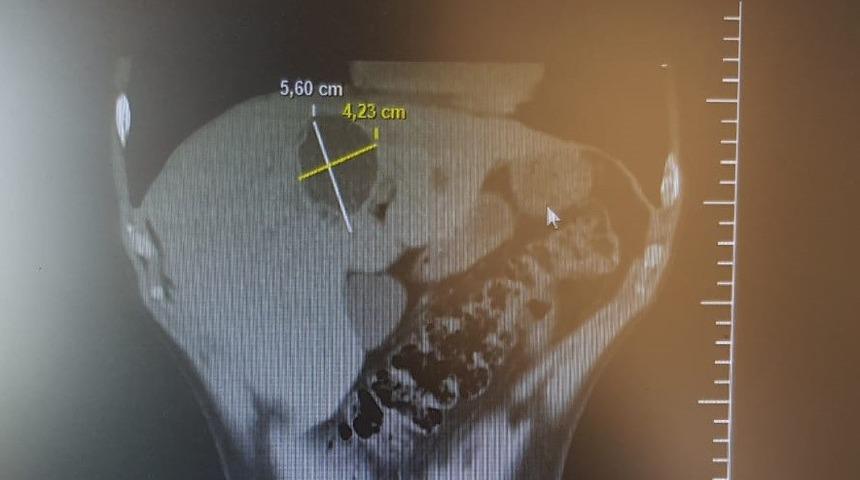

Bilecik Devlet Hastanesinde tedavi altında bulunan Sadık Akşehir (40) hasta karaciğer kist hidatik (hayvan kisti) kapalı kist ameliyatı (laparoskopik kistektomi) oldu. 5,60 ile 4,23 santimetre çapındaki kist 3 saatlik bir ameliyatın ardından alınarak, hasta 3 gün taburcu edildi. Hasta eski sağlığına kavuşurken, ameliyatı yapan Genel Cerrah Uzmanı Op. Dr. Süleyman Deniz Kahraman’a teşekkür etti.